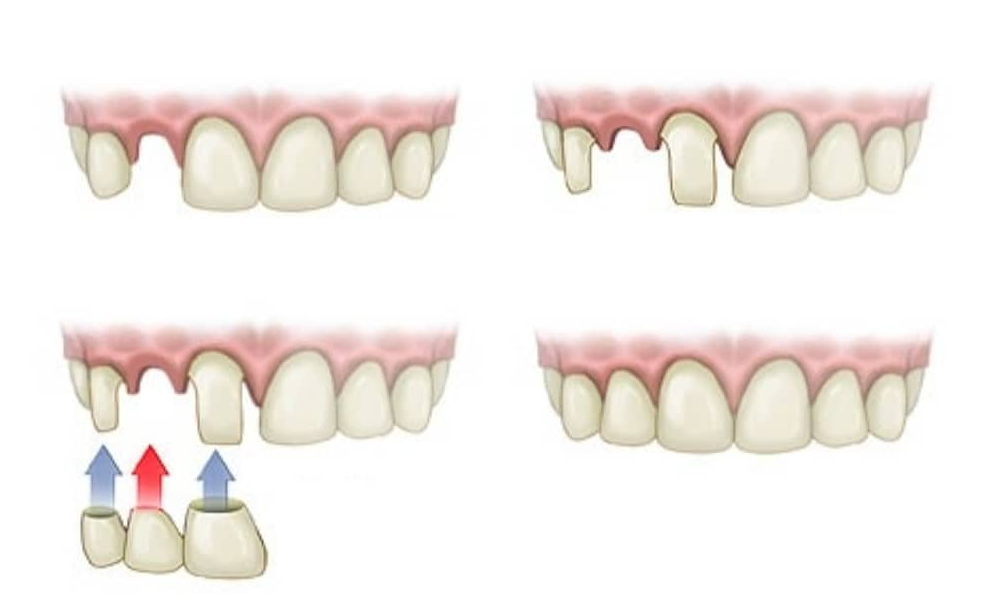

Стоматология: коронки и мостовидные протезы